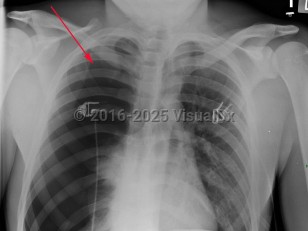

Spontaneous pneumothorax

Spontaneous pneumothorax (SP) is caused by the introduction of air between the visceral and parietal pleura, typically as the result of trauma. SP can be classified as either primary or secondary. The presence or absence of lung disease distinguishes the primary form from the secondary form. Primary SP (PSP) lacks underlying lung disease, whereas secondary SP (SSP) patients have a preexisting condition such as chronic obstructive pulmonary disease (COPD; a majority of cases), cystic fibrosis, pulmonary infection, interstitial lung disease (especially histiocytosis and sarcoidosis), AIDS, neoplasms, or drug use.

The size of the pneumothorax, rate of development, and underlying clinical status determine the clinical presentation. Those with a mild PSP may not seek care, while those with SSP present acutely. The range of signs and symptoms include acute pleuritic chest pain (localized to the side of the pneumothorax), dyspnea, decreased breath sounds, tachypnea, tachycardia, hyperresonance, unilaterally decreased lung sounds, or acute decompensation.